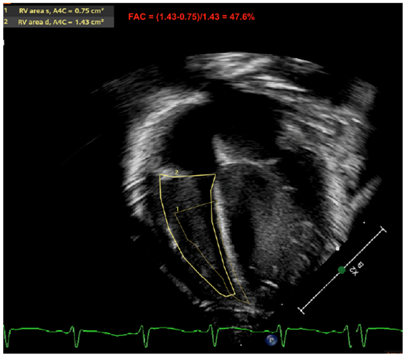

| RV-FAC | FAC is calculated after obtaining the end diastolic (EDA) and the end systolic area (ESA) of the RV (FAC = [EDA − ESA]/EDA), and also provides an important marker of RV function. Normative values have been published (although normal FAC values quoted to be most common when >35%) [35,36,37]. |

| Fractional area of change by RV | ![]() |

| Legend: The fractional area change of the RV is another marker used to estimate RV systolic function. The contour at the endocardial border is traced at the peak of systole and at the peak of diastole. The fraction ([RV End Diastolic Area] − [RV End Systolic Area])/[RV End Diastolic Area] is expressed in % of area shortening. An apical RV focused view is used. This marker may be calculated in the apical four-chamber view. Some reports have also used the RV inflow–outflow view (or RV three-chamber view, or RV “tet” view—which outlines the RV anterior and inferior walls) to compute this metric, although the American Society of Echocardiography officially recommends its evaluation in apical four-chamber view—which outlines the RV free wall and RV septum. Here, the RV-FAC is 47.6%, which is considered normal (>35%) | |